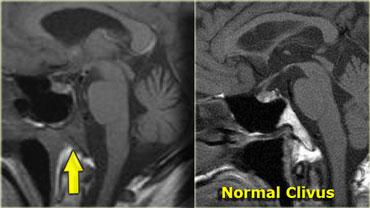

U dây sống (Chordoma)

U dây sống (chordoma) là tổn thương thường gặp nhất tại vùng xương nền (clivus), đây cũng là vị trí ưa thích của di căn và u sụn ác tính (chondrosarcoma).

Bệnh nhân này có tuyến yên bình thường.

Phía sau tuyến yên là một khối lớn dạng sùi, nằm ở vị trí tương ứng xương nền.

Hình ảnh CT cho thấy một số vôi hóa trong vùng này.

Chẩn đoán phân biệt cho khối này bao gồm u dây sống (chordoma) hoặc u sụn ác tính (chondrosarcoma).

U dây sống có xu hướng xuất hiện ở đường giữa, trong khi u sụn ác tính có xu hướng xuất hiện lệch khỏi đường giữa.

Di căn

Bệnh nhân bên trái là bệnh nhân ung thư phổi nhập viện với biểu hiện liệt dây thần kinh sọ số VI.

Bất thường nằm ở xương nền sọ (clivus), vùng này bình thường phải có tín hiệu cao trên ảnh chuỗi xung T1W mặt phẳng đứng dọc (như trong hình bên trái).

Tín hiệu thấp ở đây có nghĩa là tủy xương mỡ bình thường đã bị thay thế bởi một mô khác.

Trong trường hợp này là do di căn khối u.

U lympho, u tủy (myeloma) hoặc các bất thường xương lan tỏa cũng có thể cho hình ảnh tương tự.

Do đó, hãy luôn dành thời gian quan sát xương nền sọ (clivus).